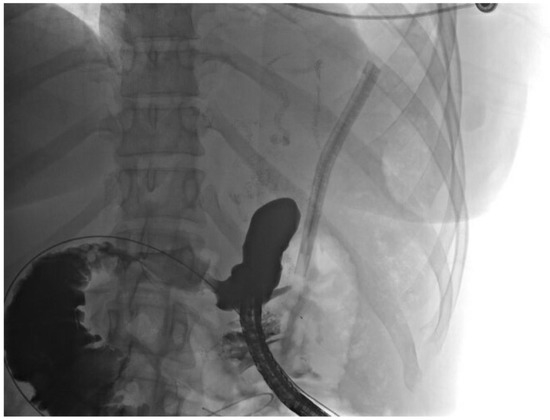

2. Detailed Case Description